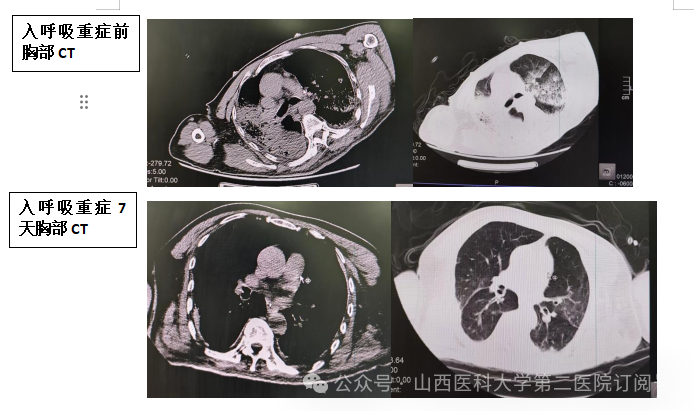

时间回溯至数周前,有慢性阻塞性肺疾病(COPD)、强直性脊柱炎病史的张先生,因脑出血合并重症肺炎、呼吸衰竭病情危急,从神经外科紧急转入呼吸与危重症医学科呼吸重症病区。刚入院时,患者生命体征极不稳定,脑出血病灶尚未稳定,慢阻肺又急性加重,重症肺炎引发的呼吸衰竭更是直逼生命红线,医护人员当即给予气管插管机械通气治疗,一场与死神的赛跑就此展开。

这场救治堪称“高空走钢丝”,多重难题接踵而至。由于张先生因强直性脊柱炎长期使用免疫抑制剂,自身免疫力严重低下,而重症肺炎治疗中既需强力抗感染,又要调控过度炎症反应。免疫力低下与炎症调控的矛盾让治疗陷入两难,抗感染与免疫平衡的把控极具挑战。更为棘手的是,脑出血救治需严格保护脑功能、严防再次出血,而重症肺炎所致的呼吸衰竭则需积极抗感染、抗炎,必要时还需抗凝治疗,两种疾病的治疗需求存在显著冲突。更加雪上加霜的是,患者多年的COPD与强直性脊柱炎导致胸廓活动受限、脊柱后凸畸形,根本无法平卧,这给机械通气参数调节、气道分泌物清除等气道管理工作带来巨大阻碍,如何在保护颅脑与救治肺脏之间找到平衡,成为摆在医疗团队面前的严峻考验。

在治疗过程中,武珈宇主治医师带领医护团队实行24小时严密监测,实时追踪患者的意识状态、生命体征、感染指标及脑功能变化,根据病情波动精准调整治疗方案。从呼吸机参数的细微调整,到抗感染药物的精准选择,再到体位护理的精心安排,每一个环节都凝聚着医护人员的专业与坚守。经过日夜不息的守护与救治,患者的感染得到有效控制,呼吸功能逐步恢复,成功撤除呼吸机,顺利转出呼吸重症监护室(RICU),经过后续康复治疗,最终达到出院标准回归家庭与社会。